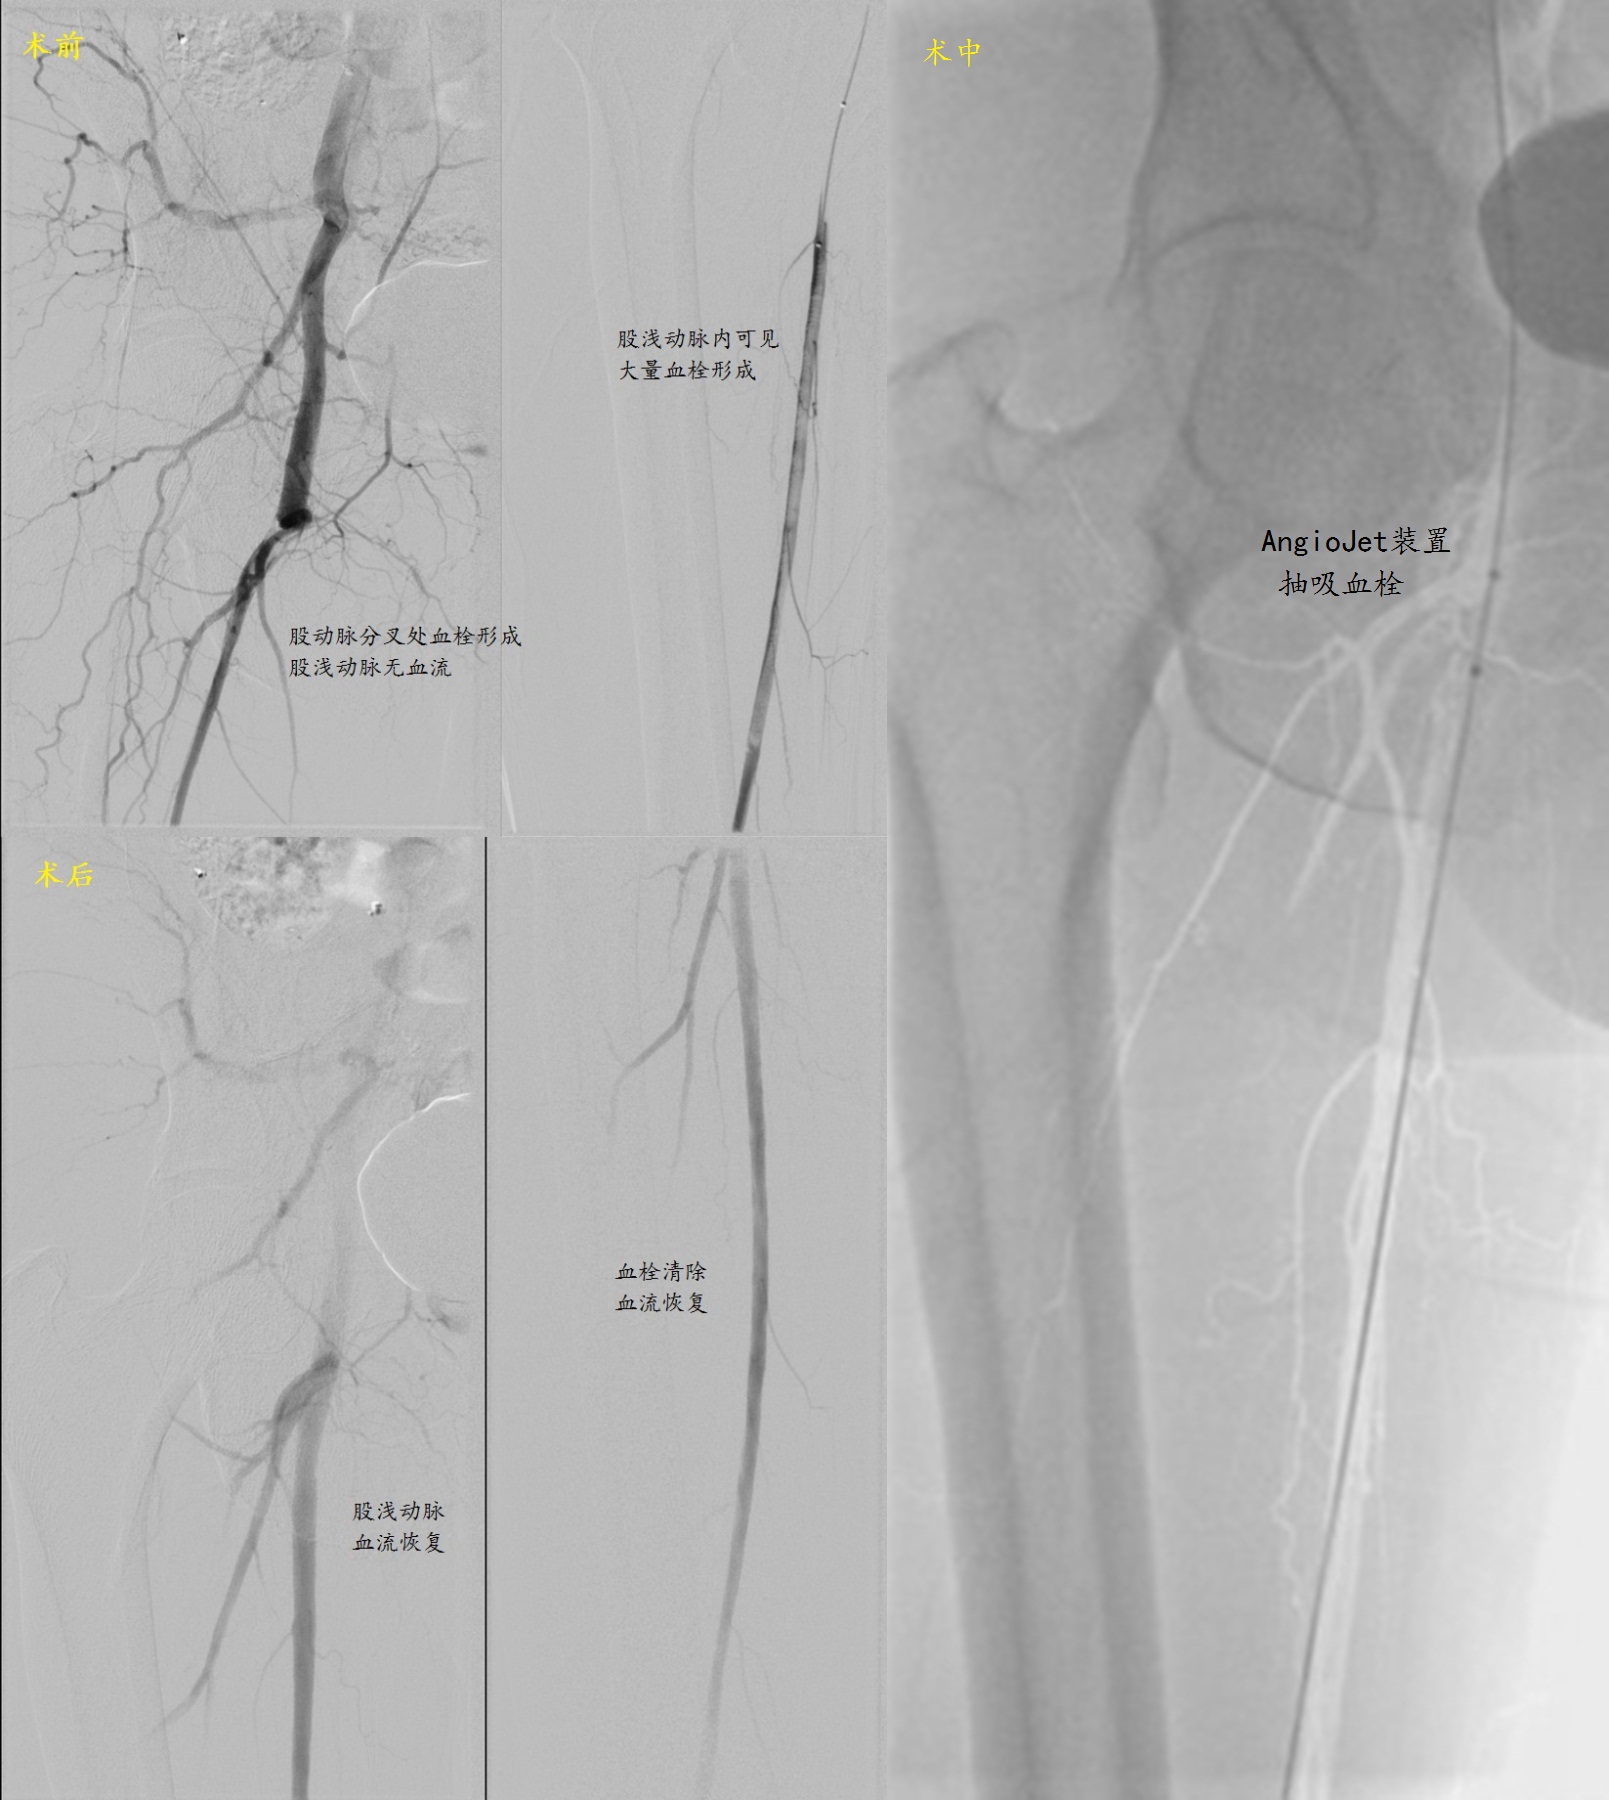

患者李伯伯1天前突发右下肢发凉、麻木,颜色紫绀,下肢动脉超声及CT造影检查明确为右侧股动脉血栓形成。股动脉是向下肢供血的主干动脉,急性缺血可导致下肢坏死。北京清华长庚医院血管外科团队使用AngioJet技术顺利抽吸动脉血栓,恢复血流供应。

术前CTA检查可见右侧股动脉血栓形成,血流中断。

血栓抽吸完成后,动脉恢复通畅血流。